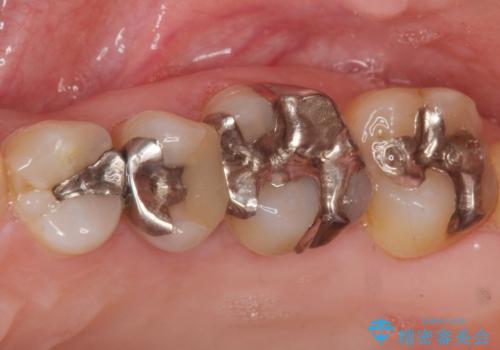

- 歯の根のあたりの歯ぐきを押すと痛むことを主訴に来院された患者様です。

精査したところ、左上の小臼歯(左上5)の神経が死んでいました。

根管治療後、セラミッククラウンによる補綴を行いました。